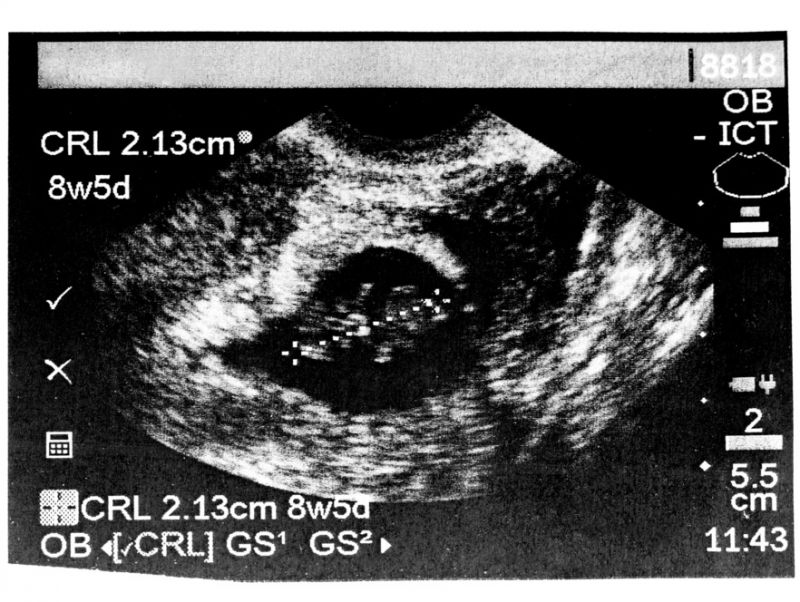

Arkansas is the latest state to advance legislation that would significantly limit the time period in which women can legally obtain an abortion. On Wednesday, the state Senate’s Public Health, Welfare and Labor Committee approved a bill that would outlaw an abortion if a doctor can detect a fetal heartbeat—which can occur as early as six weeks into gestation.

Senate Bill 134 amounts to a near-total ban on abortion, as it often takes women six weeks to realize they are pregnant at all (especially when the pregnancy is unplanned). It would also cut off access to abortion well before fetal abnormalities or other conditions are apparent. More to the point, even finding a heartbeat that early in a pregnancy requires sticking a probe inside the woman’s vagina. This is basically Transvaginal Ultrasounds: The Sequel, except far worse, since it would deny a woman the right to have an abortion after having a plastic wand shoved inside her.